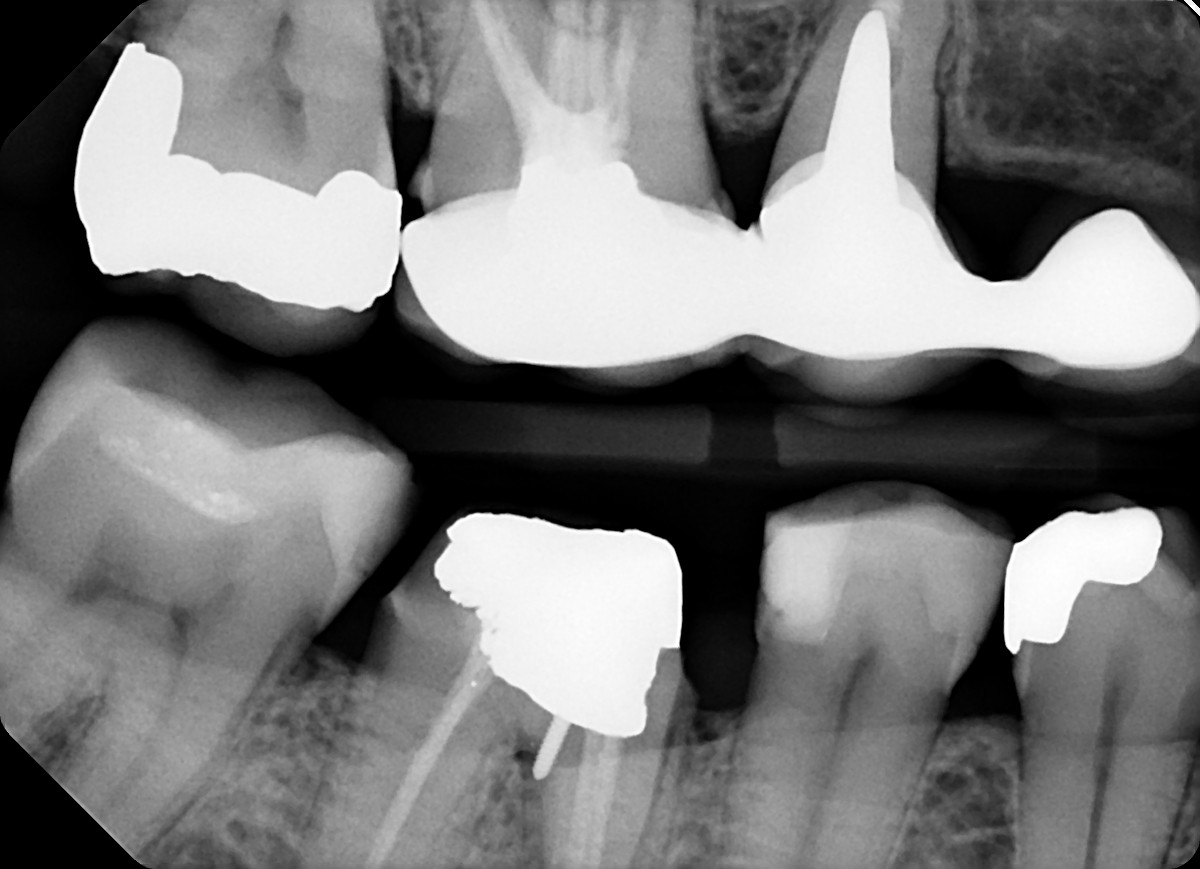

13. What option can be selected for the restoration on the lower jaw?